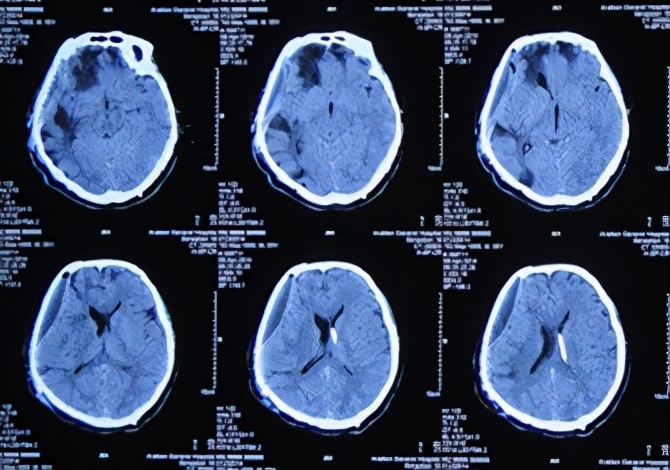

患者于2013年9月17日凌晨因车祸致头部外伤、昏迷,急诊于山东省聊城市某医院就诊,头CT检查发现双额及右颞叶多发脑挫裂伤并右侧脑室受压、中线左移(图-1),当天进行了右侧额颞叶脑挫裂伤血肿清除并去骨瓣减压术,术后头CT:去骨瓣减压术后状态(图-2)。

图-1:2013年9月17日术前头CT

图-2:2013年9月17日术后头CT